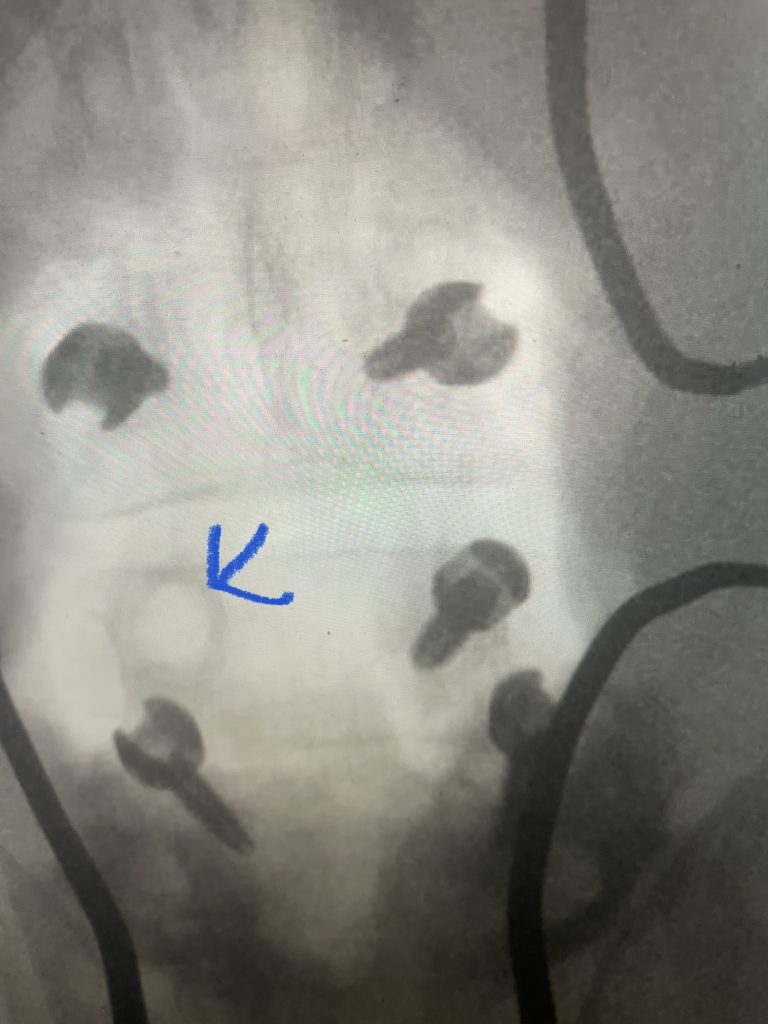

Fig 3: Demonstrating the Misonix ultrasonic emulsifier to safely remove bone without injuring the dura and soft tissues.

Other maneuvers are always having a ready feeling of letting go of the tissue, having a light touch like “pumping your brakes”. Also, it is sometimes necessary to “shovel” the tissue, not bite it, with the Kerrison (Fig 2), utilizing the device as a dissecting instrument as well. It is also important to be patient and take the tissue in two bites, if necessary. It is ok to bite thickened tissue incompletely with the Kerrison if one is not sure if the consequence would be a leak or tear in the membrane if adhesions are present; dissect the adhesion with a Penfield 4 and cut it with a Metzenbaum scissors and then proceed with the finishing bite. The older patients are particularly challenging given the quality of their dura; it is often quite thin and floppy. A useful technique is employing an ultrasonic device (Fig 3) to remove enough of a shelf of bone to gain a dissection plane to allow for Kerrison to take over. And one can start with a 1 or 2 mm Kerrison to make a start under the edge of the bone and compressive soft tissue and advance to a 3 or 4mm.